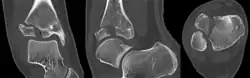

Tillaux fracture

A Tillaux fracture is a Salter–Harris type III fracture through the anterolateral aspect of the distal tibial epiphysis.[1] It occurs in older adolescents between the ages of 12 and 15 when the medial epiphysis had closed but before the lateral side has done so,[2] due to an avulsion of the anterior inferior tibiofibular ligament, at the opposite end to a Wagstaffe-Le Fort avulsion fracture